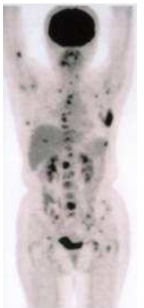

74.下圖是何種檢查所呈現之影像?

(A)MRI (B)ultrasonography (C)computed tomography (D)PET whole body scan